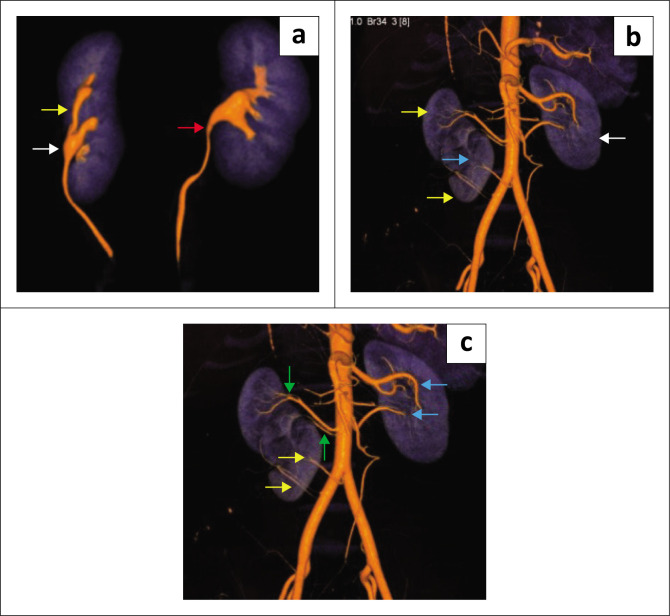

Supernumerary kidney (SK) is an uncommon anomaly of the urinary tract, usually occurring on the left side. A rare case of a partially-fused, SK on the right side is presented. The diagnosis is made through the identification of a distinct pelvicalyceal system along with its supplying renal artery and vein, utilising ultrasound, CT, or MRI.

Contribution: Correct diagnosis of partially-fused, supernumerary kidneys based on imaging is crucial to avoid unnecessary procedures, so that asymptomatic cases are managed conservatively.